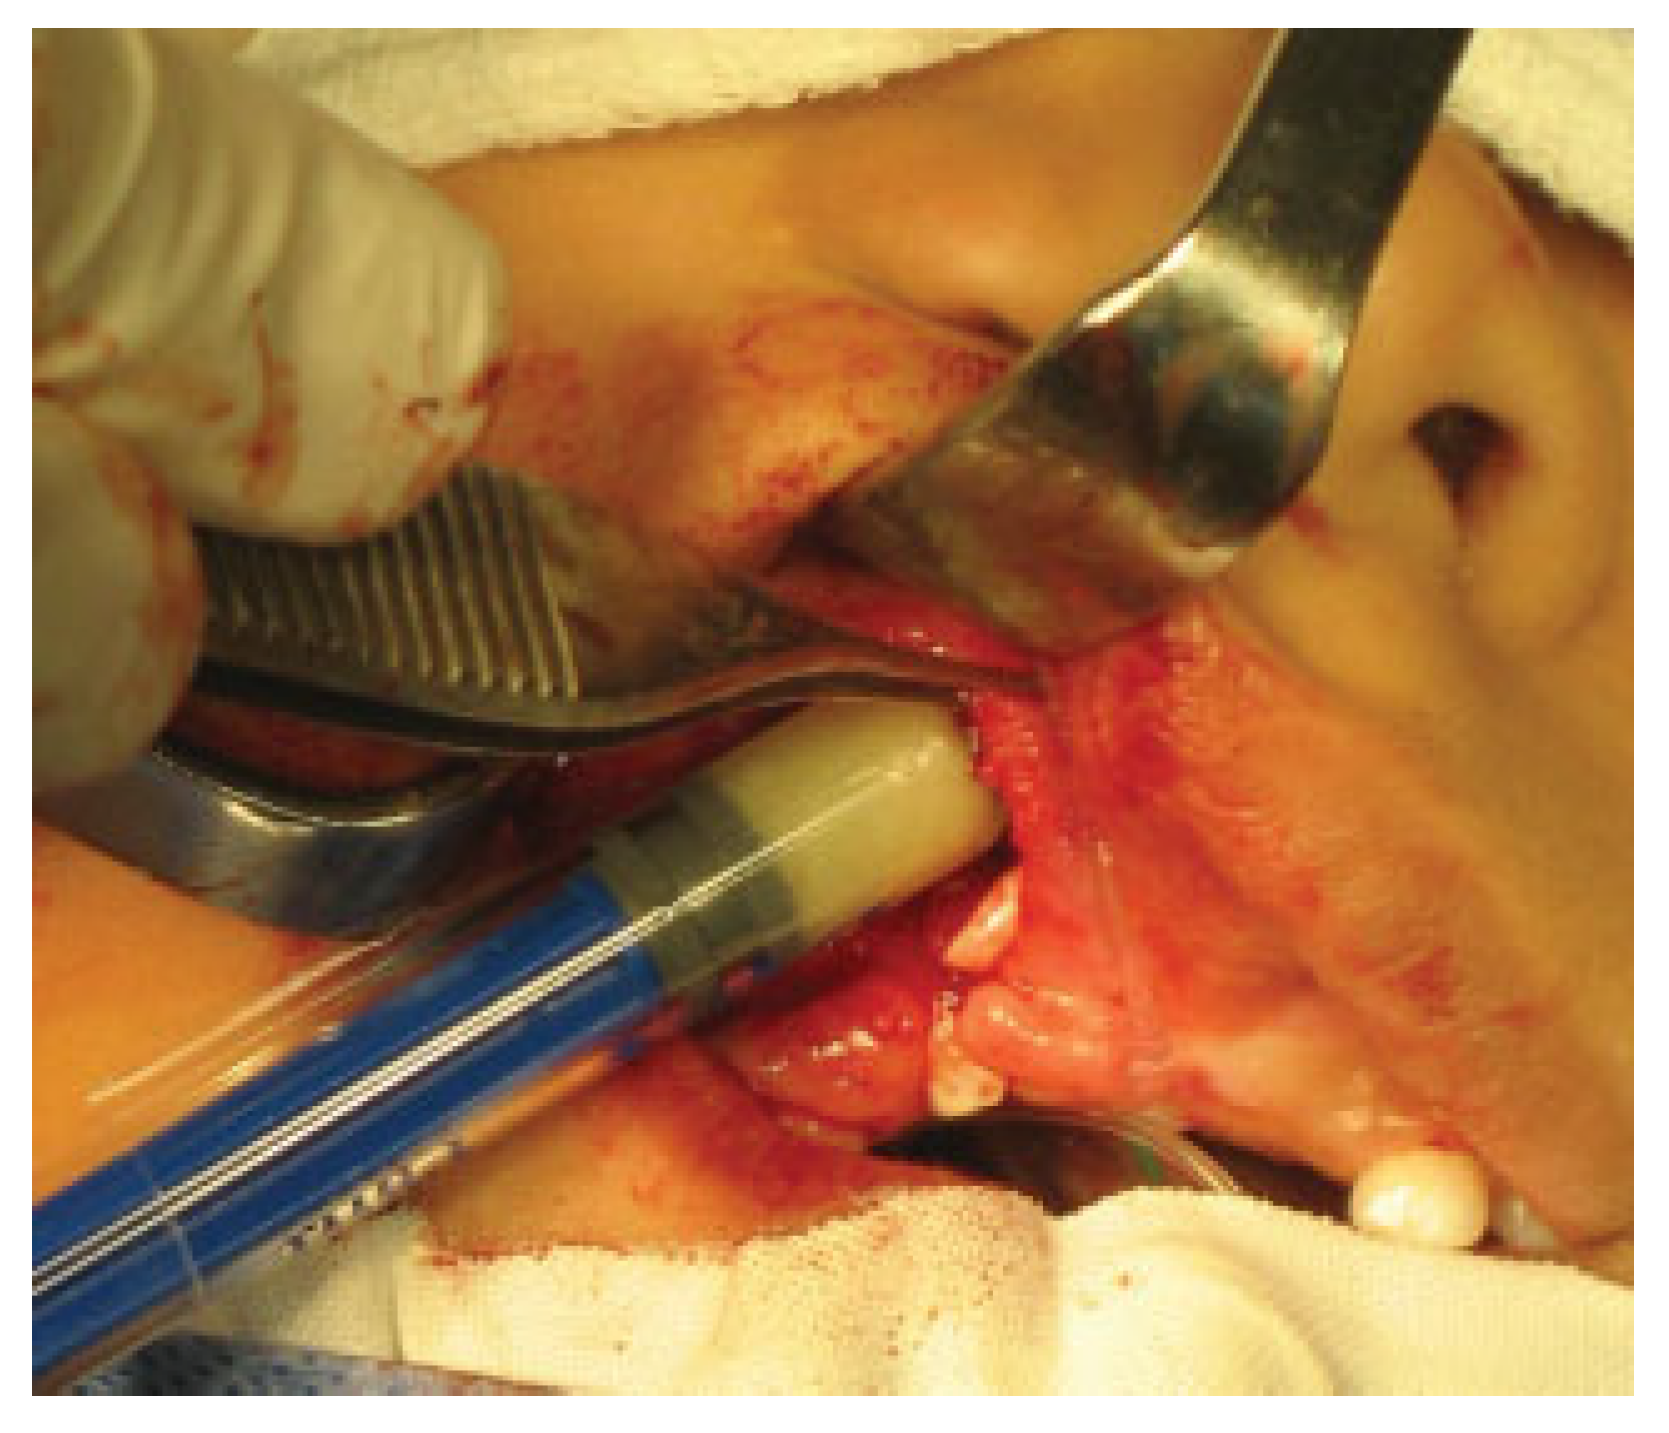

The putty or the iliac crest bone graft was taken and packed into the alveolar cleft between the cortical bone edges (►Figure 2) and then the lateral gingivoperiosteal flap is advanced to cover the cleft and is sutured to the smaller medial (anterior) flap and to the palatal flaps (►Figure 3). In patients with bilateral clefts, the same flap design was used. During the surgical procedure, a dose of cephazolin was administered and once the surgical procedure was finished, the patients were discharged with oral cephalexin for 7 days and liquid diet for 4 weeks.

Figure 2.

Introduction of the DBM DBX putty in the alveolar cleft.